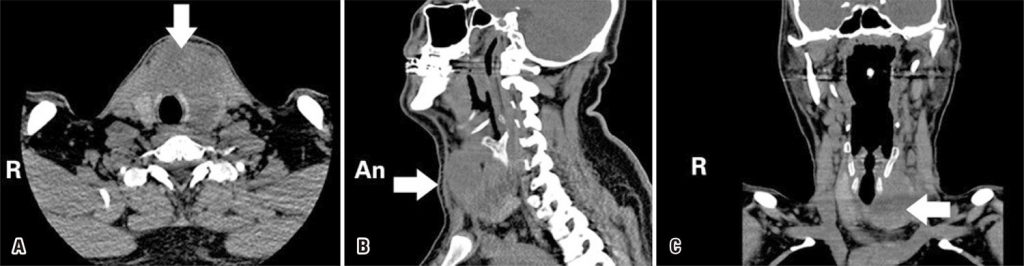

A tireoidite supurativa aguda é uma emergência endócrina muito rara e com risco de vida. A tireotoxicose é uma doença rara, que acompanha a tireoidite supurativa aguda. A maioria dos casos descritos na literatura tem diferentes causas, mas o desenvolvimento espontâneo é muito raro. Relatamos o caso de um paciente com tireoidite supurativa aguda, que veio a nossa clínica apresentando achados tireotóxicos, e o comparamos com a literatura. Trata-se de paciente do sexo masculino, 31 anos, que foi internado em nossa clínica com queixa de dor progressiva, edema e vermelhidão na linha média do pescoço, febre e palpitações. Ao exame físico, foram observados edema, vermelhidão e sensibilidade à dor na região do pescoço, consistente com a localização da tireoide. Apresentava tremor de mãos, taquicardia e agitação. Embora os exames de função tireoidiana fossem compatíveis com tireotoxicose, houve achados que sustentavam a presença de infecção nos exames bioquímicos. Nas avaliações radiológicas, observou-se lesão heterogênea dividida por pequenos septos, com áreas de consolidação no lobo tireoidiano esquerdo. Na biópsia por aspiração por agulha fina, foi possível aspirar apenas 2mL de líquido purulento, devido à presença de pequenas áreas de consolidação separadas umas das outras. Iniciaram-se antibioticoterapia, administração de propranolol e esteroides, além de tratamento sintomático. Eikenella corrodens cresceu na cultura do antibiograma. A antibioticoterapia foi estendida por 14 dias devido à melhora nos sintomas e dos valores bioquímicos. Após o tratamento, o paciente se apresentava eutireoideo, com melhora na febre e na vermelhidão no pescoço, sendo então acompanhado. Deve-se ter em mente que a tireoidite supurativa aguda pode se desenvolver espontaneamente com achados de tireotoxicose, sem nenhum fator de risco.